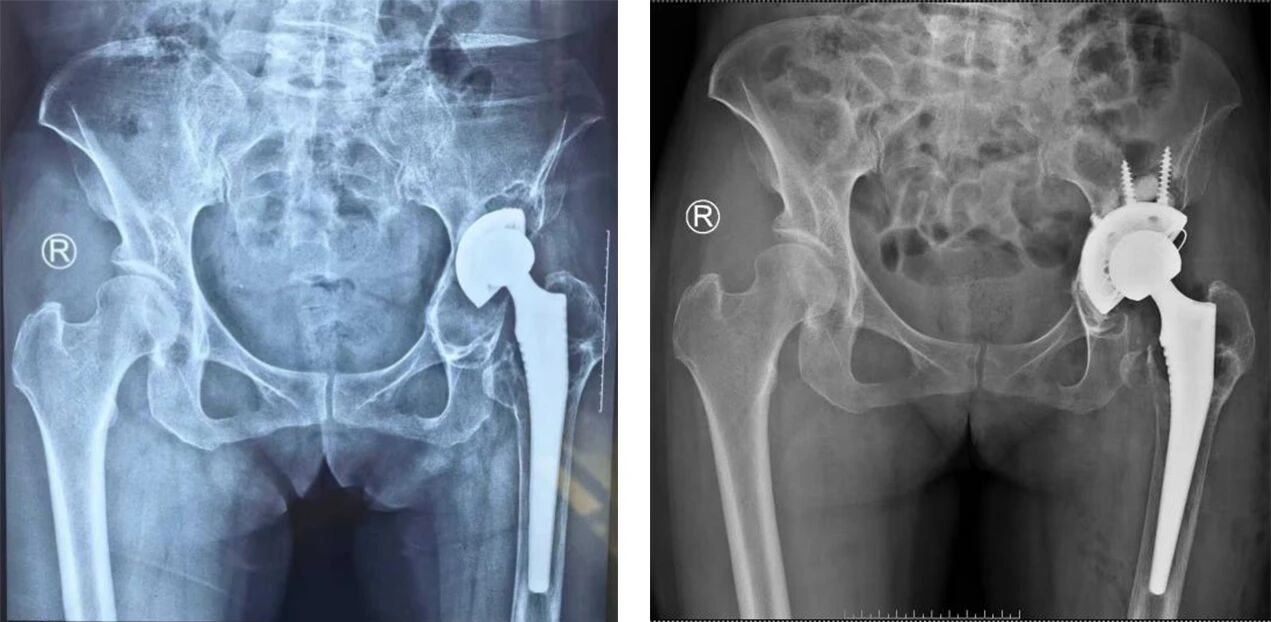

近日,駐馬店市第一人民醫(yī)院急診外科成功為一名左側(cè)人工髖關(guān)節(jié)假體松動(dòng)患者實(shí)施全髖關(guān)節(jié)翻修術(shù)。57歲的關(guān)女士在11年前因左側(cè)股骨頭壞死接受人工全髖關(guān)節(jié)置換,術(shù)后恢復(fù)良好。1年前,她無(wú)明顯誘因出現(xiàn)左髖部疼痛,并逐漸出現(xiàn)下肢不等長(zhǎng)、行走跛行,經(jīng)檢查確診為假體松動(dòng)。

入院后,急診外科孫海濤醫(yī)生為患者進(jìn)行詳細(xì)查體,結(jié)合影像學(xué)檢查明確診斷為髖臼側(cè)假體松動(dòng)??剖医?jīng)討論制定個(gè)性化手術(shù)方案,在麻醉科、心內(nèi)科等多學(xué)科協(xié)作下,順利完成左側(cè)人工全髖關(guān)節(jié)翻修術(shù)。

全髖關(guān)節(jié)翻修手術(shù)相較于初次置換手術(shù)難度更高,面臨患者骨骼條件變差、可能存在骨缺損及需精準(zhǔn)取出原有假體等挑戰(zhàn)。目前,駐馬店市第一人民醫(yī)院已建立成熟的翻修手術(shù)診療體系,通過經(jīng)驗(yàn)豐富的團(tuán)隊(duì)、全面的術(shù)前評(píng)估、適合翻修手術(shù)的先進(jìn)假體材料以及多學(xué)科協(xié)作下的科學(xué)康復(fù),為手術(shù)成功提供保障。